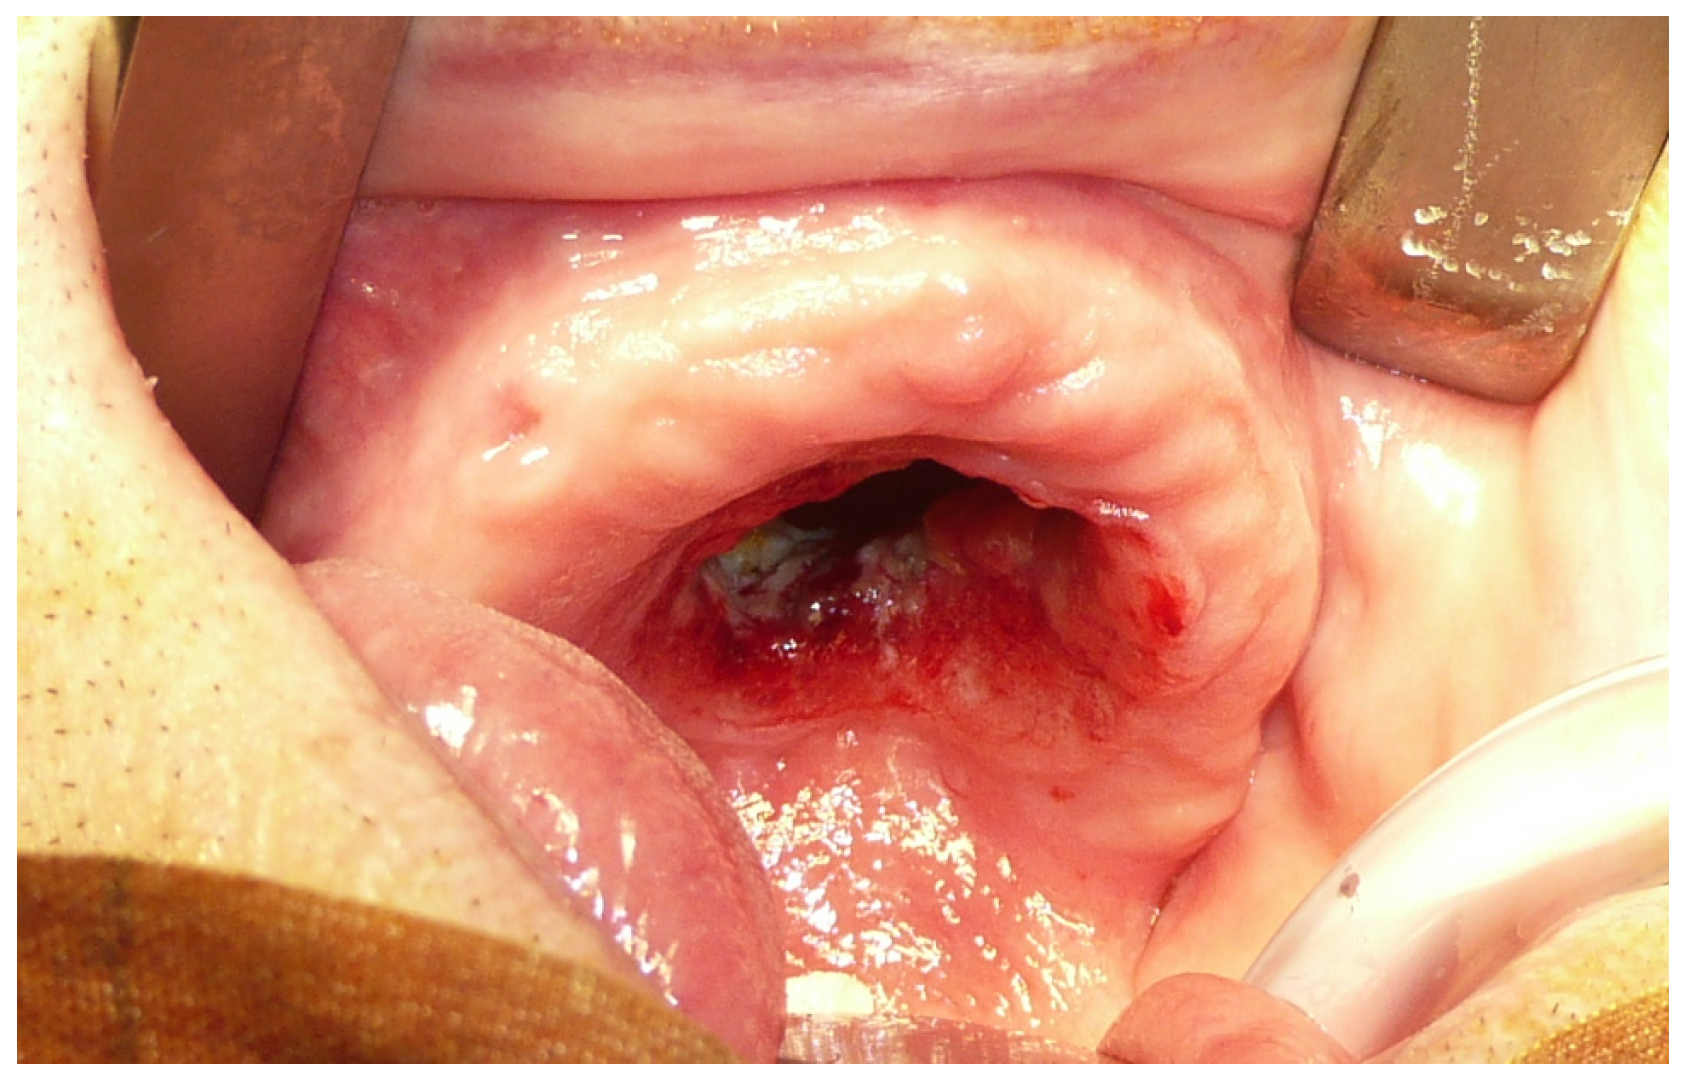

A 90-year-old man was referred to the Maxillofacial Surgery division of the University Hospital of Sassari on the discovery of an ulcerated lesion of the palate, present for approximately two months [Figure 1]. The patient had multiple comorbidities in his medical history: a previous ethmoidectomy for squamous cell carcinoma (22 years earlier), arterial hypertension, a prior cerebral stroke, hypercholesterolemia, and arterial disease of the lower limbs.

Figure 1.

Pre-operative view of the maxillary tumor.